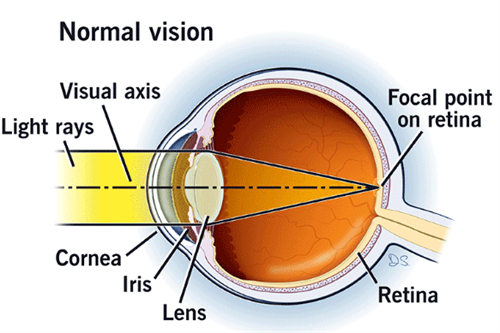

糖尿病视网膜病变,也被称为糖尿病性视网膜病变或糖网病。它是由于糖尿病导致视网膜微血管受损,进而影响视力。